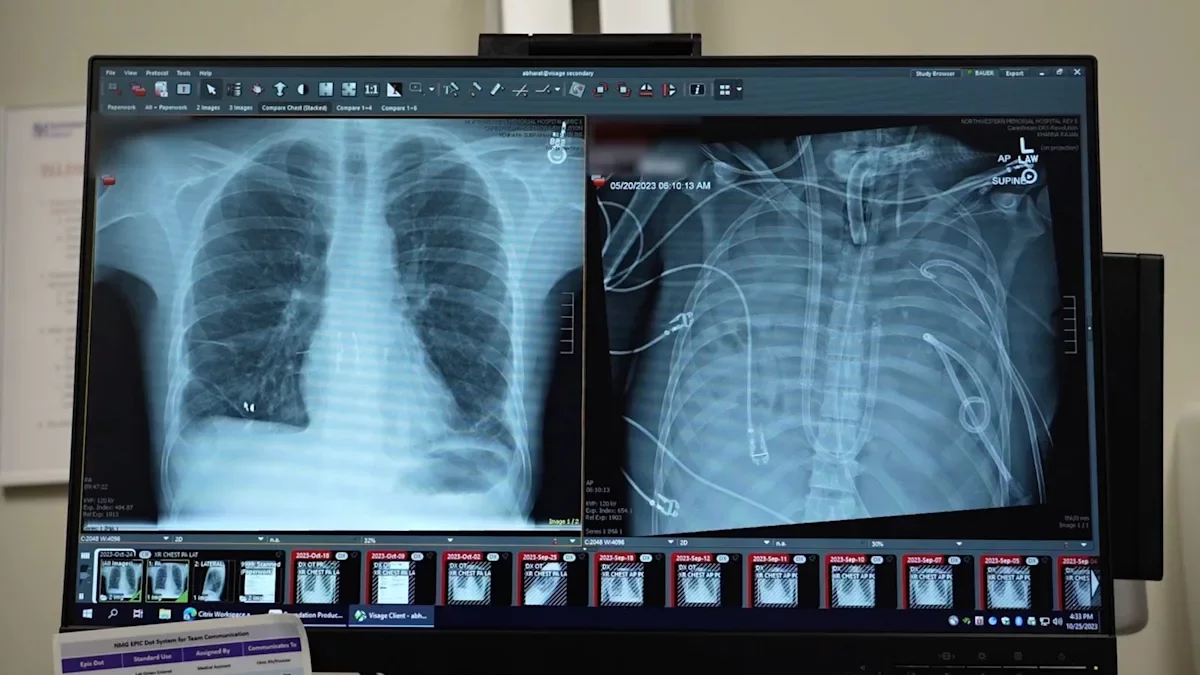

Cuando llegó al hospital, "el paciente estaba en estado crítico. Su corazón se paró en cuanto llegó y tuvimos que hacerle una reanimación cardiopulmonar (RCP)", recuerda Ankit Bharat, cirujano torácico en la Universidad Northwestern de Chicago (Estados Unidos), y autor principal del estudio cuyos detalles se han publicado este jueves en la revista Med de Cell Press.

Para ello, el equipo diseñó un sistema extracorpóreo de pulmón artificial que sustituyó temporalmente las funciones pulmonares. El sistema oxigenaba la sangre, eliminaba el dióxido de carbono y ayudaba a mantener un flujo sanguíneo estable a través del corazón y el cuerpo.

Cuando se retiraron los pulmones infectados, la condición del paciente mejoró, su presión arterial se estabilizó, la función de los órganos se recuperó y la infección remitió.